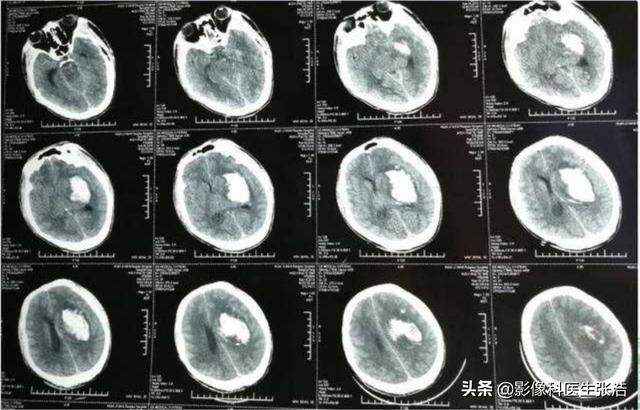

上の画像は、脳の左基底核領域に二次性脳出血を発症した高血圧患者のCT画像である。

慢性的な血圧上昇を放置した場合の最も一般的な合併症は脳卒中である。虚血性脳卒中であれ出血性脳卒中であれ、その結果は個人にとって破滅的なものとなる。

(3)高血圧脳症:血圧が急に上昇して頭蓋骨や脳を圧迫しすぎると、脳循環障害や脳出血まで起こり、軽症の場合は嗜眠や錯乱などの神経学的異常が現れ、重症の場合はジェット嘔吐や昏睡、四肢の機能異常も見られる。

脳虚血や脳出血を引き起こす血管の破裂

同様に、脳の血管も動脈硬化の影響を受けやすく、血流不足や血栓が閉塞を起こすと、一過性脳虚血は軽微な問題だが、虚血性脳梗塞は重篤な問題となる。血管が破裂すると出血性脳梗塞を起こす!

(2)脳:高血圧は脳血管の病変を引き起こし、脳出血、脳血栓症、一過性脳虚血発作、その他の中枢神経系疾患の原因となる;

脳血管障害:高血圧は脳の細い血管のけいれんを引き起こし、頭痛、頭の腫れ、目のかすみ、耳鳴り、物忘れ、不眠などの症状を引き起こす。血圧が急激に大きく上昇すると高血圧性脳症になり、激しい頭痛、嘔吐、けいれん、昏睡などの頭蓋内圧亢進の症状が現れます。高血圧性脳症は、脳出血や脳梗塞などの脳卒中にもつながることがあります。 脳出血は、高血圧患者が排便のために力むと起こることがあるので、精神的ストレスや排便のために力むことを避けるようにする必要があります。